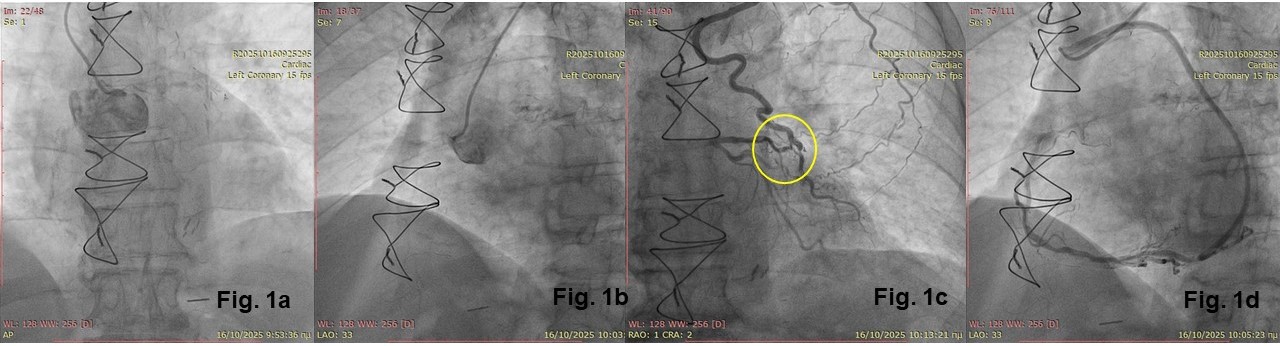

Coronary angiography revealed total occlusion of both the left coronary artery and the RCA at their ostial origins (Figure 1A and B). The LIMA graft showed severe stenosis (90%) at the anastomotic end (Figure 1C), while the radial artery graft to the distal RCA was patent (Figure 1D). Interestingly, the LIMA graft was anastomosed to a major diagonal branch rather than the LAD (Video 1).